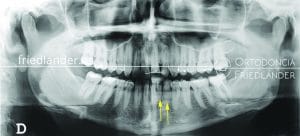

El siguiente tratamiento con Invisalign Full es de un paciente de 34 años que acude a nuestra consulta por motivos estéticos. Ya en la primera visita se observó la clase II (mandíbula retruída) y desviada hacía la izquierda; y una tendencia a la mordida abierta por deglución atípica. (la lengua empuja los dientes en lugar de subir al paladar a la hora de tragar).

Después de hacer el estudio de ortodoncia que hacemos en todos los casos, se decidió junto con el paciente de seguir adelante con Invisalign y elásticos para acabar de mejorar la oclusión (la mordida) del paciente consiguiendo una clase I (que es la relación correcta que buscamos). Explicamos al paciente que la corrección de una clase II de esta magnitud, 4-5mm, es complejo pero con una buena colaboración por su parte se podría hacer (se tiene que colocar los elásticos durante casi todo el tratamiento).